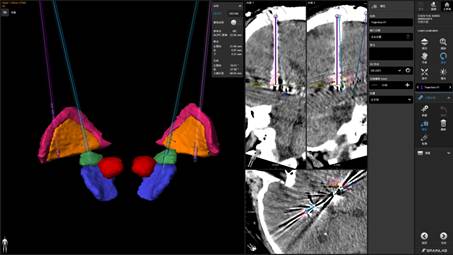

与传统方案相比,四通道DBS系统如同为大脑安装了“双核双靶点”的精准刺激系统。医生在双侧大脑的特定核团中各植入一根拥有多个触点的电极,通过独立的四个通道进行刺激。其多靶点覆盖特性可应对Meige综合征多部位受累的问题,多样化的刺激组合模式能完成精细化参数调整,定向刺激还能减少电流扩散,在提升疗效的同时最大程度避免副作用。

手术由本部神经外科副主任谭守刚DBS功能团队联合中国人民解放军总医院专家完成。凭借丰富的经验和娴熟的技术,在立体定向框架与多模态影像融合技术的引导下,将电极精准植入预设核团。

术后给予低电量刺激时,患者眼睑及面部的抽动现象即刻得到改善。术后复查显示,电极位置精准,达到预期目标。术后第三周,患者经神经调控后症状改善非常满意。

电极位置精准